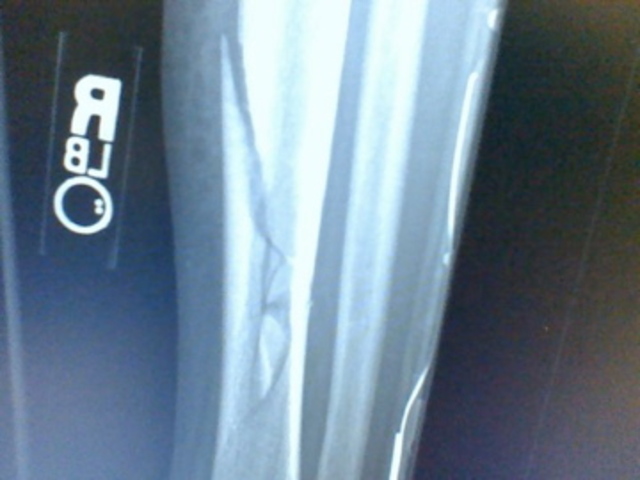

• Breaking my leg

Breaking my leg

I broke my leg skiing, and was on crutches for three months with three different casts, and wore a boot for two more months.